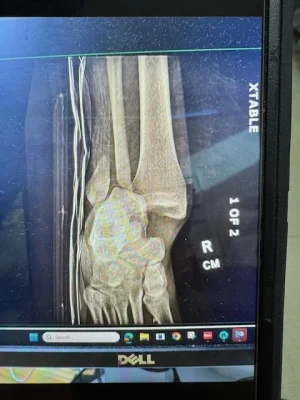

Son Facetimed me yesterday and all I heard was screaming and cussing. I got him calmed down and he showed me foot, it was flopping and hanging sideways. Doing surgery tomorrow and orthopedic said "if all goes well you will be in a boot in 4 weeks and good to go in 8 weeks". Anyone have any experience with something like this? I have broke several bones but nothing below the waist. The only time he got upset was worrying about playing baseball this fall. The picture below is his ankle, he is laying on his back and his foot should be pointing up.